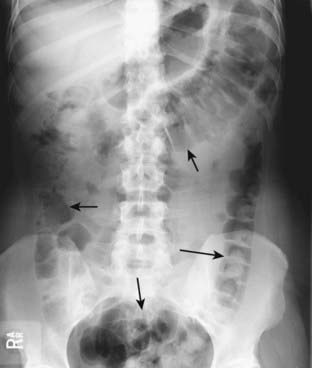

Figure 13-7 Location of large bowel.

The large bowel usually occupies the periphery of the abdomen. The small bowel is located more centrally. Here, the large bowel (solid black arrows) contains a normal amount of air. The liver occupies the right upper quadrant and normally displaces all bowel from this area.